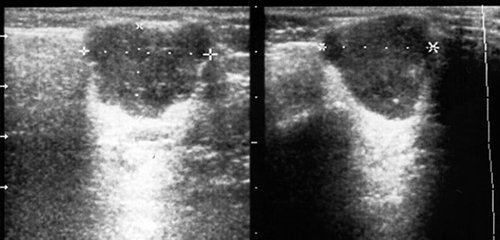

Рис. 4. Острый серозный лимфаденит в левой околоушной железе (в двух плоскостях сканирования).

Рис. 5. Острый серозный лимфаденит в левой околоушной железе с ограниченным периаденитом.